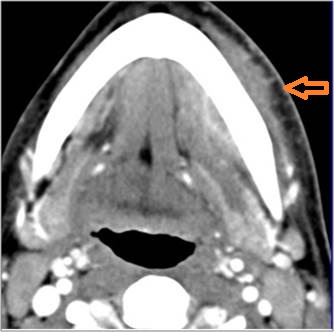

There is evidence of thrombus, thrombophlebitis or other occlusive or inflammatory process of the jugular vein or smaller venous tributaries.